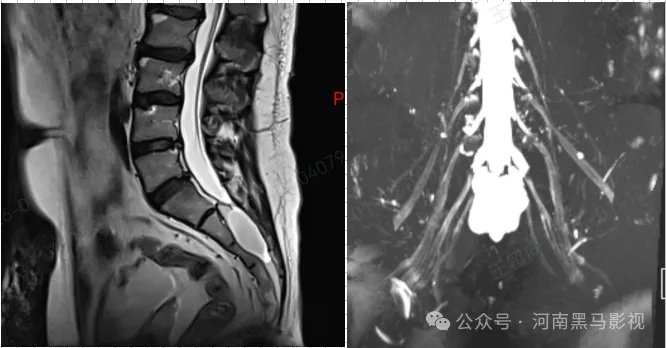

刘先生腰骶部疼痛2年余,久坐久站后加重,严重影响生活。辗转多家医院,查腰椎MRI显示骶管囊肿,但被告知骶管囊肿不需要干预治疗。刘先生年龄不大,没有椎间盘突出,椎管狭窄等腰椎退变,这两年来几乎都是按照腰肌劳损给予药物及物理治疗,均未消除病痛。刘先生偶然通过网络查询到北京积水潭医院郑州医院开设有“骶管囊肿专病门诊”,遂来就诊。

核磁共振(MRI)是目前诊断和鉴别骶管囊肿首选方法,是骶管囊肿诊断的“金标准”。但是,目前大多数人对骶管囊肿普遍缺乏正确认识,导致临床中被延误诊治的情况时有发生。